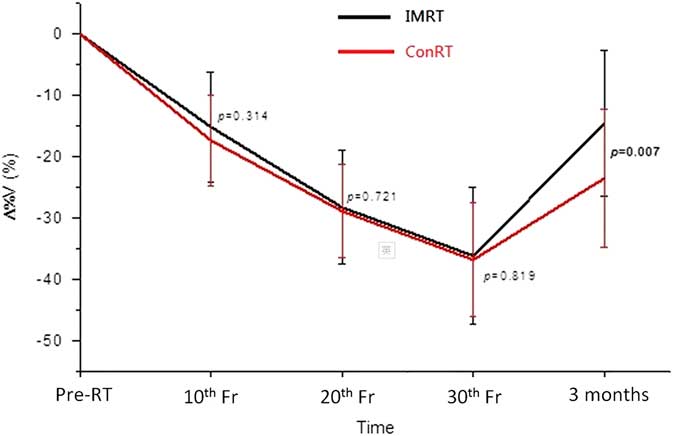

Percentage parotid volume change

The mean parotid volume in both groups decreased with a maximum reduction of 35% at the 30th fraction (Figure 3). There were no significant differences between the ConRT and IMRT groups from 10th to 30th fractions. Volume recovery was observed in both groups at 3 months following RT with significantly greater recovery in the IMRT group (p=0·007). The trend of DSC was similar to that of the volume change. It decreased from pre-treatment to 30th fraction and partially recovered at 3 months after treatment (Figure 4). Significant difference between ConRT and IMRT was only noted at the 3 months post-RT interval with the IMRT group demonstrating a better restoration of the original shape (p=0·003).

Figure 3 Comparison of the mean percentage change of volumes of parotid glands between conventional radiotherapy (ConRT) and intensity-modulated radiotherapy (IMRT) plans over the radiotherapy course up to 3 months after treatment. Note: The horizontal lines indicate the error bars.

With regard to the geometric changes of the parotid gland during radiotherapy, our study demonstrated that there were no significant differences between patients treated by ConRT and IMRT. For both groups of patients, the parotid gland demonstrated continuous shrinkage and medial migration during the treatment course. They were reflected by the increase of Δ%V, DSC and TVD from pre-treatment to 30th fraction, respectively. The shrinkage of parotid glands during radiotherapy has been reported in previous studiesReference Barker, Garden and Ang 16 , Reference Zhang, Lin and Wu 17 and it was mainly caused by the loss of gland parenchyma and acinar cell atrophy due to high dose radiation.Reference Radfar and Sirois 18 , Reference Wang, Yan and Zhang 19 The volume reduction of the parotid gland subsequently changed its shape and therefore resulted in a similar trend in DSC as for Δ%V. This medial migration of the parotid gland during radiotherapy was caused by the shrinkage of radiosensitive NP tumour, which was situated medially to the parotid gland and created space for the parotid gland to move in. Another associated factor could be due to the weight loss of the patients, whose head size became smaller leading to the lateral structures moved closer to the mid-plane. Actually such medial movement of the parotid gland during radiotherapy course has been reported by some studies.Reference Fung, Wu and Teo 20 , Reference Barker, Garden and Ang 21 Our study has shown that NPC patients generally had gradual weight loss during a course of radiotherapy. This was reflected by the reduction of the lateral head dimension. The phenomenon of weight lost, however, may vary across other institutions depending on nutritional support given. This is a common phenomenon for head and neck cancer patients as a result of poorer nutritional status due to radiation induced oral mucositis and xerostomia. The effect would be compounded with concurrent chemotherapy, which is commonly applied for stage II disease or above for NPC patients.

Due to the better target dose conformity in IMRT plans, they were more effective in sparing the parotid gland than the conRT plans in NPC patients. This was proven in our study in which the average mean parotid dose of the IMRT group was about 12 Gy lower than that of the ConRT group. This was also the reason that higher prescribed dose to the target could be given in IMRT than in ConRT plans, which subsequently led to better tumour control.Reference Au, Ngan and Ng 22 , Reference Yan, Cao and Wang 23 Although the geometric changes of the ConRT group appeared relatively greater than that of the IMRT group during the radiotherapy course, their differences did not reach significance. This implied that the extra dose delivered by the ConRT to the parotid gland did not lead to significant geometric change during the treatment course. The possible reasons were because the mean doses of both groups had already exceeded the recommended tolerance mean dose of 25 Gy,Reference Deasy, Moiseenko and Marks 24 the extra dose delivered by the ConRT would not cause significant increase of parotid gland damage. Nevertheless, the results obtained at 3 months after treatment demonstrated that IMRT plans showed better recovery of parotid gland volume, shape and centroid position. For instance, the mean parotid volume returned to 85% of pre-treatment volume in IMRT group, compared with 75% in ConRT group. This indicated that although the rate of parotid gland damage was similar during the course of radiotherapy, the rate of recovery after completion of treatment was different between the two techniques. It has been reported that parotid recovery took place after completion of radiotherapyReference Hey, Setz and Gerlach 25 which were in line with the geometric changes obtained in our study. In addition, study by Hey et al.Reference Hey, Setz and Gerlach 25 reported that the recovery process of the parotid gland could be dose dependent. It was also proposed in some studies that stem cells in the parotid gland were responsible for the post-RT repair if they were not eliminated in the treatment course.Reference Feng, van der Zwaag, Stokman, van Os and Coppes 26 As the more conformal IMRT plans are better equipped to limit the high dose to a smaller volume, and deliver lower mean dose to the gland, it can help to preserve more stem cells in the gland and facilitate better recovery. The improved recovery of the parotid gland in the IMRT cohort may be attributed to this improved opportunity for stem cell recovery.